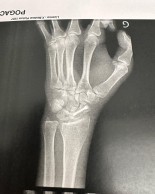

Desde que Tadej Pogacar sufriera una caída y la lesión en el hueso escafoides de una de sus manos se ha especulado si el esloveno sería capaz de afrontar el Tour de Francia 2023 con plenas garantías, sobre todo, teniendo en cuenta el excelente estado de forma mostrado por Jonas Vingegaard en Critérium du Dauphiné. ¿Podrá Tadej Pogacar estar a la altura de su gran rival?

Han pasado dos meses desde que Tadej Pogacar se rompiera el escafoides de su mano izquierda. Un huesecillo pequeño pero que a la mayoría de los mortales trae de cabeza cuando sufren esa lesión a ser un elemento clave en el gesto de agarre, no digamos ya si lo que hay que sujetar es el manillar de una bicicleta.